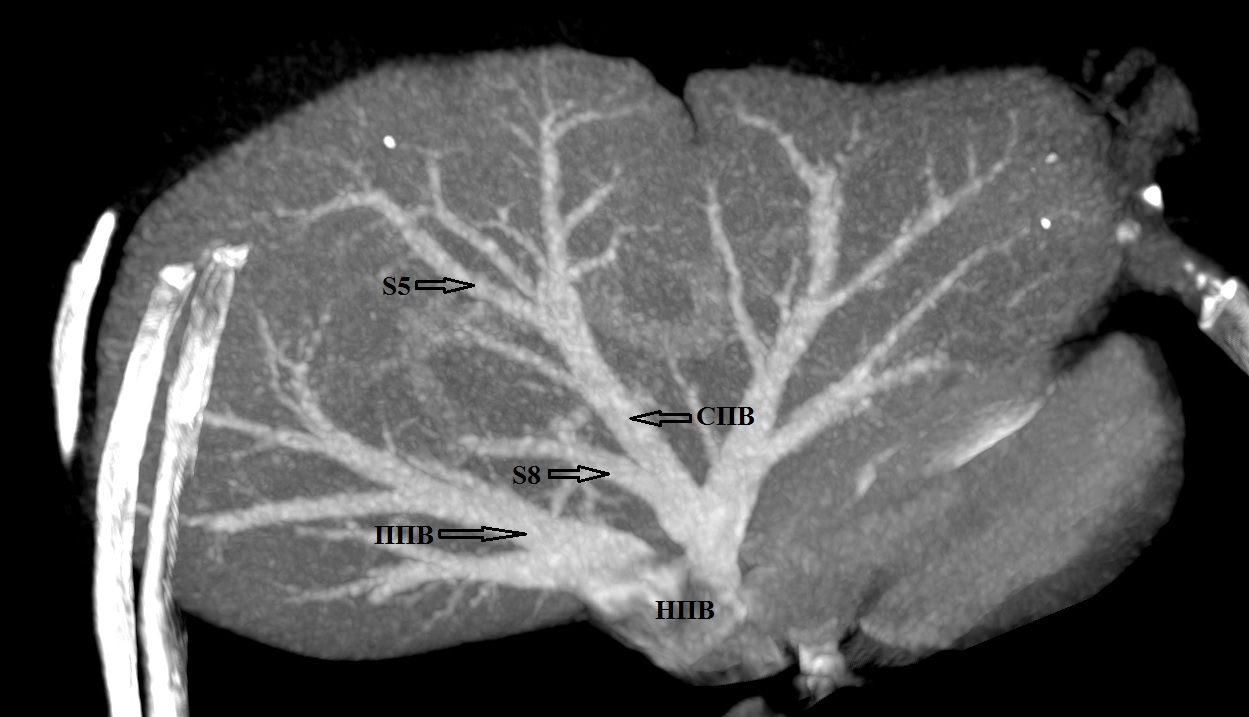

9. Тип С (снимок КТ). | |

| Тема | ||

| Тип | Исследовательские инструменты | |

Посмотреть

(159KB)

|

Метаданные ▾ | |